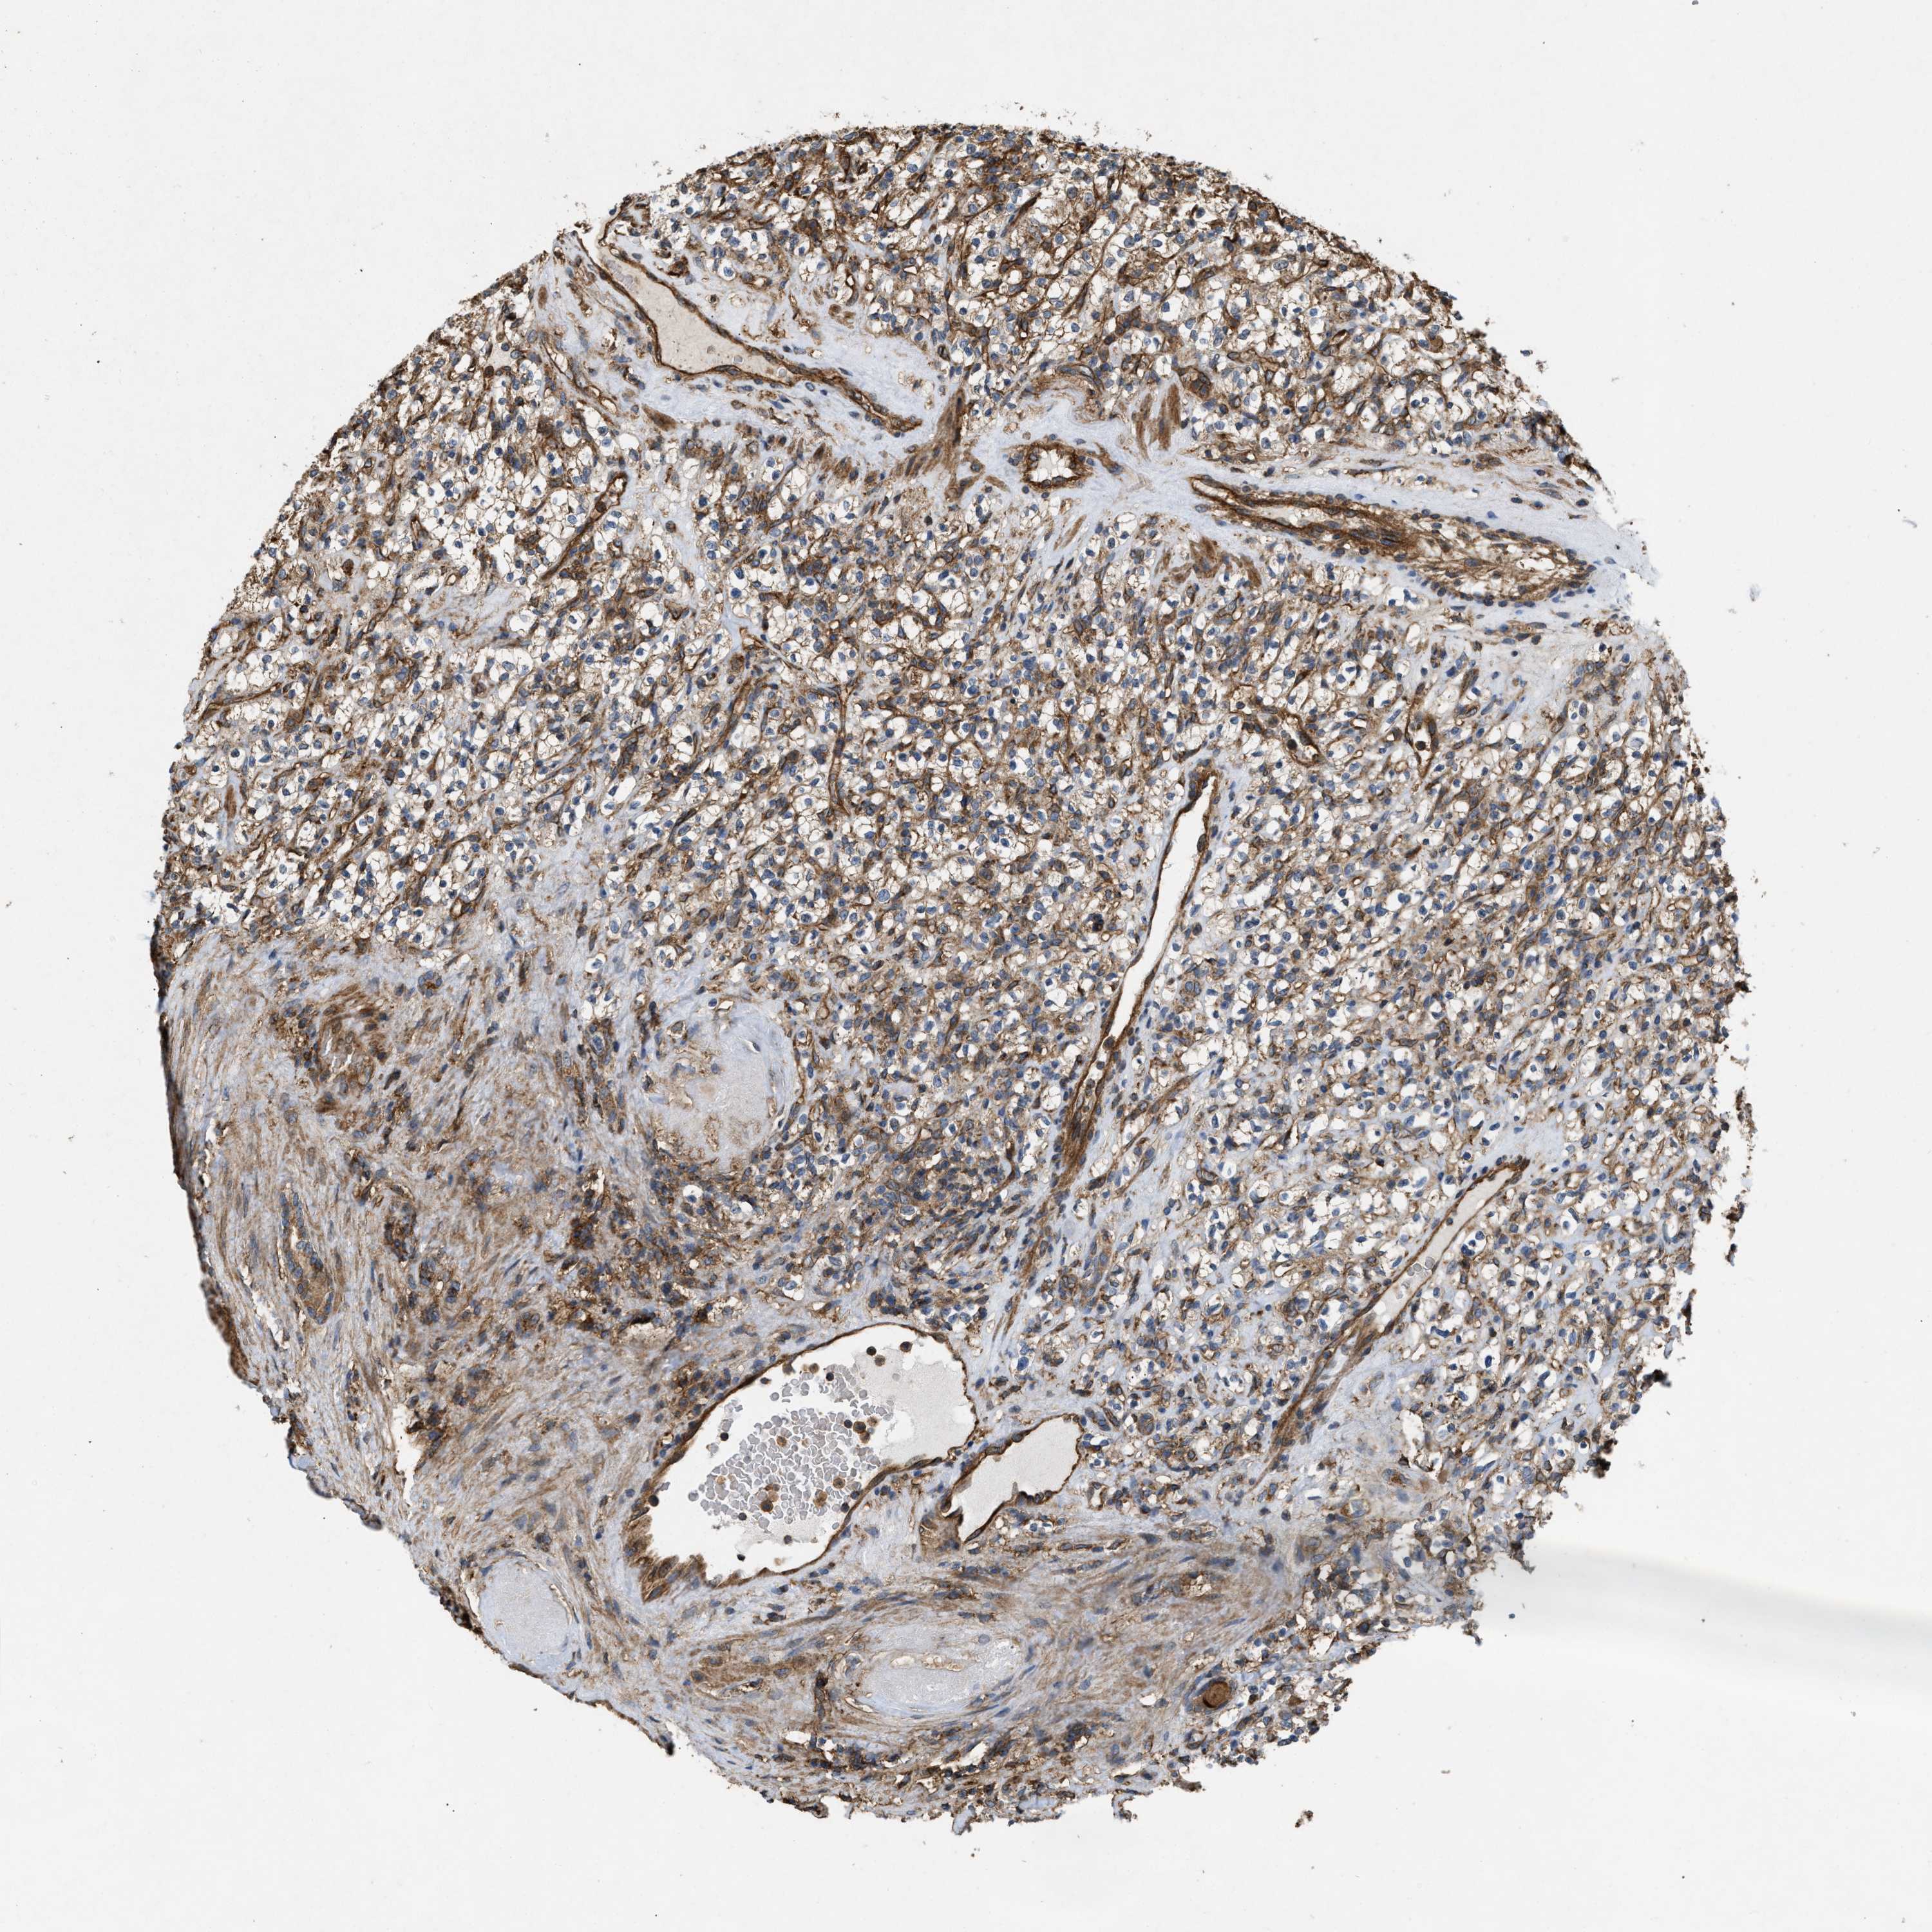

KIDNEY RENAL CLEAR CELL CARCINOMA (TCGA) - Interactive survival scatter ploti

The Survival Scatter plot shows the clinical status (i.e. dead or alive) for all individuals in the patient cohort, based on the same data that underlies the corresponding Kaplan-Meier plots. Patients that are alive at last time for follow-up are shown in blue and patients who have died during the study are shown in red.

The x-axis shows the expression levels (FPKM) of the investigated gene in the tumor tissue at the time of diagnosis. The y-axis shows the follow-up time after diagnosis (years). Both axes are complimented with kernel density curves demonstrating the data density over the axes. The top density plot shows the expression levels (FPKM) distribution among dead (red) and alive patients (blue). The right density plot shows the data density of the survived years of dead patients with high and low expression levels respectively, stratified using the cutoff indicated by the vertical dashed line through the Survival Scatter plot. This cutoff is automatically defined based on the FPKM cutoff that minimizes the p-score. The cutoff can be changed by dragging the vertical line or by entering a cutoff value in the square labeled "Current cut-off".

Under the Survival Scatter plot the p-score landscape (black curve; left axis) is shown together with dead median separation (red curve; right axis). Dead median separation is the difference in median mRNA expression between patients who have died with high and low expression, respectively. It is calculated as follows: median FPKM expression of dead patients with high expression - median FPKM expression of dead patients with low expression. This is intended to aid the user in visually exploring custom cutoffs and the associated p-scores and dead median separation.

Individual patient data is displayed and can be filtered by clicking on one or more of the category buttons on the top of the page. Categories describing expression level and patient information include: high, low, alive, dead, female, male and tumor stages. The scale of the x-axis can be toggled between linear and log-scale by clicking on the "x log" button. Mouse-over function shows TCGA ID, patient information and mRNA expression (FPKM) for each patient.

& Survival analysisi

Kaplan-Meier plots summarize results from analysis of correlation between mRNA expression level and patient survival. Patients were divided based on level of expression into one of the two groups "low" (under cut off) or "high" (over cut off). X-axis shows time for survival (years) and y-axis shows the probability of survival, where 1.0 corresponds to 100 percent.

GNB4 is not prognostic in Kidney Renal Clear Cell Carcinoma (TCGA)

Best expression cut offi

Based on the FPKM value of each gene, patients were classified into two groups and association between prognosis (survival) and gene expression (FPKM) was examined. The best expression cut-off refers the FPKM value that yields maximal difference with regard to survival between the two groups at the lowest log-rank P-value. Best expression cut-off was selected based on survival analysis .

When clicking on this number, the vertical dashed line indicating cut-off, the interactive survival plot, and the Kaplan-Meier curve will be adjusted to show results based on the best expression cut-off.

: 13.69

Median expressioni

Median expression refers to the median FPKM value calculated based on the gene expression (FPKM) data from all patients in this dataset. When clicking on this number, the vertical dashed line indicating cut-off, the interactive survival plot, and the Kaplan-Meier curve will be adjusted to show results based on the median expression.

: N/A

Median follow up timei

Median follow up time refers to the median time (years) after diagnosis with this type of cancer, based on clinical data from all patients in this dataset.

P scorei

Log-rank P value for Kaplan-Meier plot showing results from analysis of correlation between mRNA expression level and patient survival.

N/A

5-year survival highi

5-year survival for patients with higher expression than the expression cutoff.

For melanoma and glioma, 3-year survival is shown.

5-year survival lowi

5-year survival for patients with lower expression than the expression cutoff.

TCGA RNA samplesi

RNA-seq data is reported as average FPKM (number Fragments Per Kilobase of exon per Million reads), generated by the The Cancer Genome Atlas (TCGA) .

Normal distribution across the dataset is visualized with box plots, shown as median and 25th and 75th percentiles. Points are displayed as outliers if they are above or below 1.5 times the interquartile range. FPKM values of the individual samples are presented next to the box plot.

Average pTPM 14.2

Number of samples 521